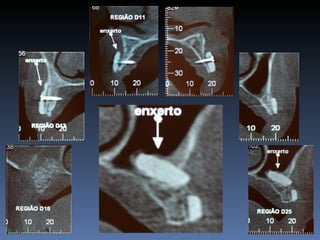

Data- 24-04-2012

Diagnóstico: Desdentado parcial

bi-maxilar

Plano de tratamento: Reabilitação das áreas

desdentadas 1.5, 1.6, 4.6 reabilitadas com aloenxertos

ósseos frescos-congelados, para posterior reabilitação

pretética.

Área previamente enxertada

Aumento de volume ósseo vertical

Exposição precoce do bloco “onlay”